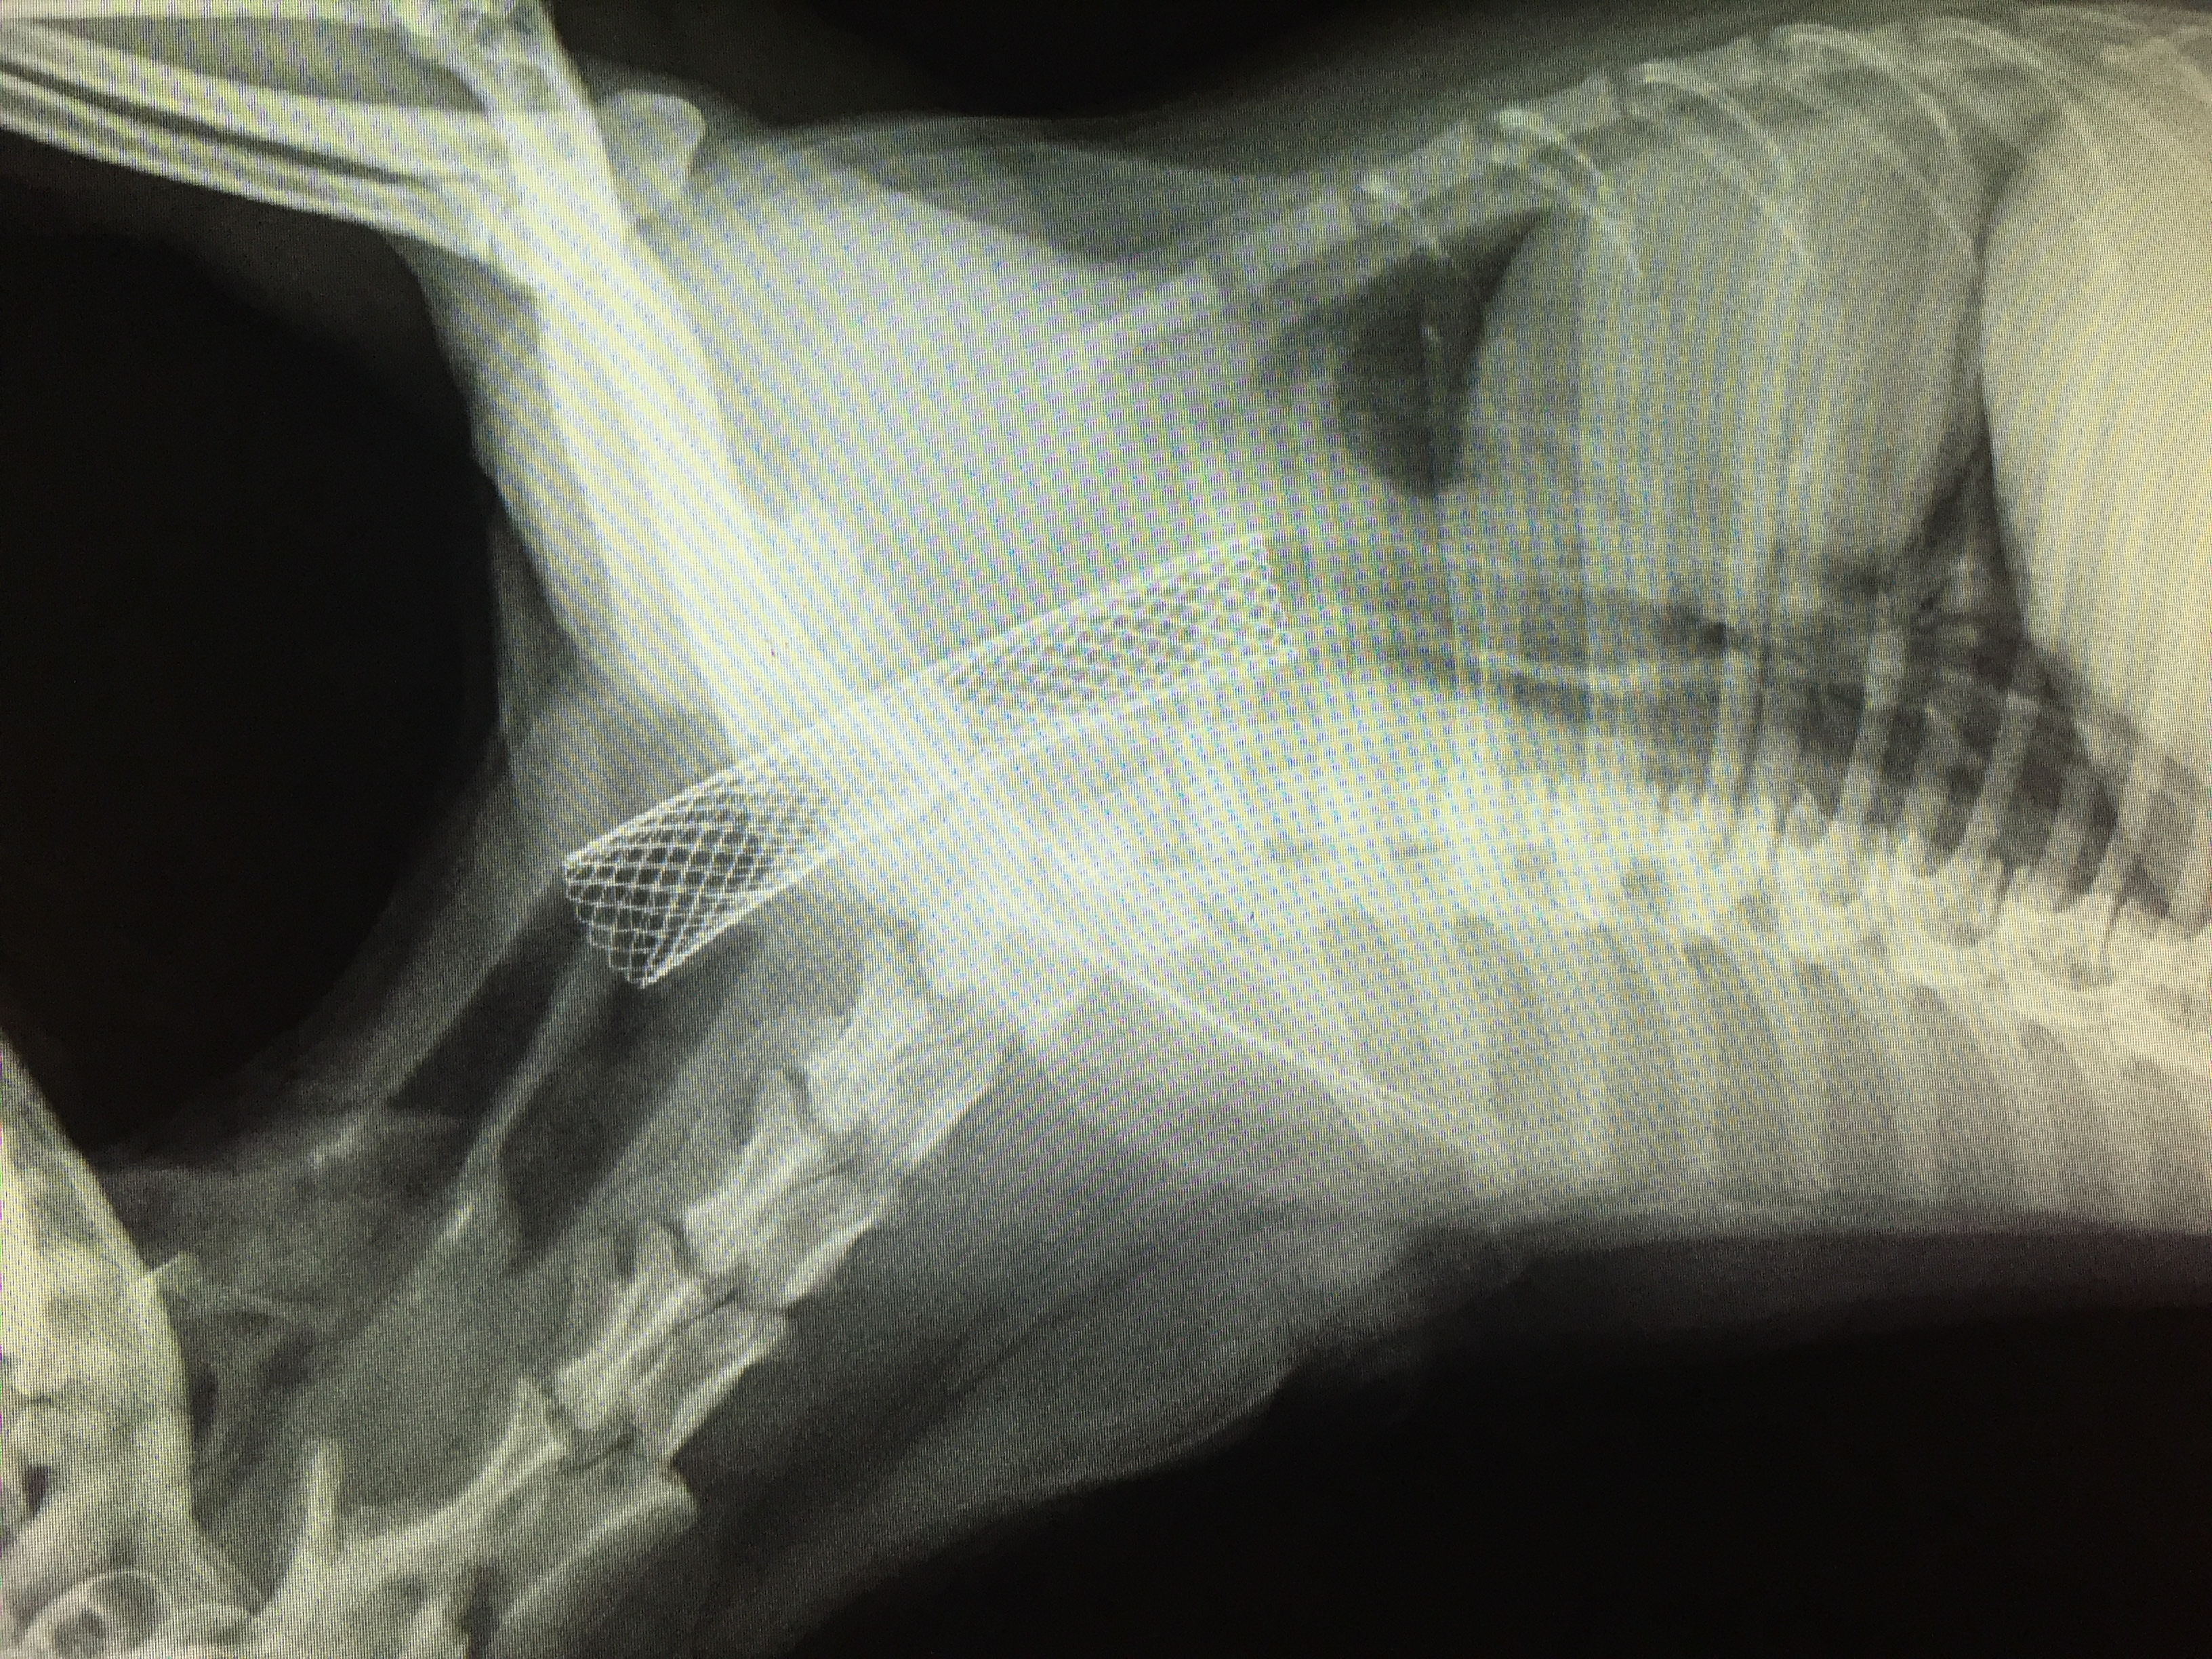

Коллапс трахеи форум